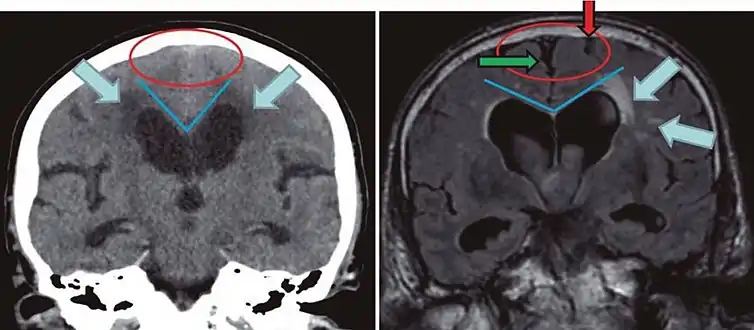

Leukoaraiosis is a particular abnormal change in appearance of white matter near the lateral ventricles. It is often seen in aged individuals, but sometimes in young adults.[1][2] On MRI, leukoaraiosis changes appear as white matter hyperintensities (WMHs) in T2 FLAIR images.[3][4] On CT scans, leukoaraiosis appears as hypodense periventricular white-matter lesions.[5]

The term "leukoaraiosis" was coined in 1986[6][7] by Hachinski, Potter, and Merskey as a descriptive term for rarefaction ("araiosis") of the white matter, showing up as decreased density on CT and increased signal intensity on T2/FLAIR sequences (white matter hyperintensities) performed as part of MRI brain scans.

These white matter changes are also commonly referred to as periventricular white matter disease, or white matter hyperintensities (WMH), due to their bright white appearance on T2 MRI scans. Many patients can have leukoaraiosis without any associated clinical abnormality. However, underlying vascular mechanisms are suspected to be the cause of the imaging findings. Hypertension, smoking, diabetes,[3] hyperhomocysteinemia, and heart diseases are all risk factors for leukoaraiosis.